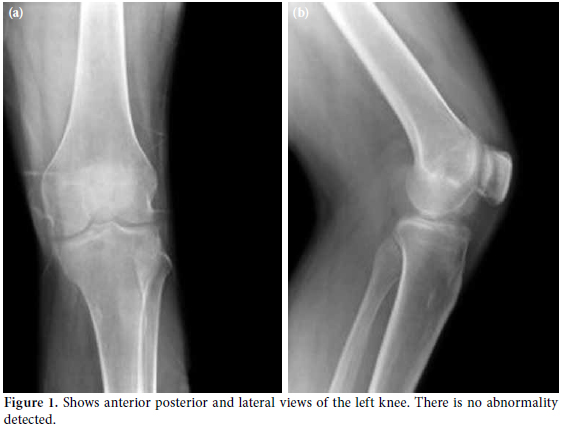

Laboratory investigations were unremarkable with the exception of elevated uric acid levels (611 umol/L). A plain radiograph of the left knee showed no abnormalities (Figure 1). Subsequently, magnetic resonance imaging (MRI) was ordered to determine the cause of the locked knee, and it showed minimal joint effusion with a hypointense soft tissue mass encasing the anterior cruciate ligament (ACL) and posterior cruciate ligament (PCL) measuring 5.7x1.5x2.2 cm. The MRI of the left knee in the axial, coronal, and sagittal sections revealed a nonspecific mass encasing the left ACL and PCL ligament with minimal joint effusion, which was suggestive of a synovial sarcoma of the left knee joint (Figure 2).